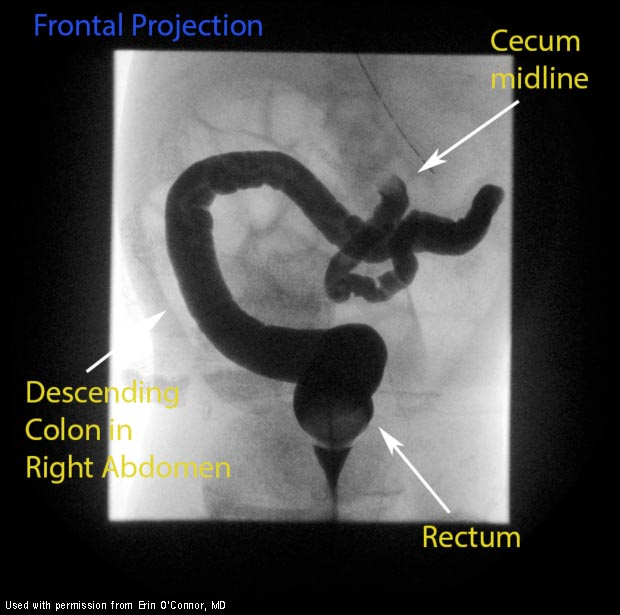

Anatomy of malrotation (as seen on barium enema)

What is the key to diagnosing malrotation?

Identification of the location of the ligament of Treitz

Usually, it is on the left side of the abdomen underneath the stomach.

In malrotation, it is attached to the right abdominal wall and crosses over the cecum. (Ladd’s bands)